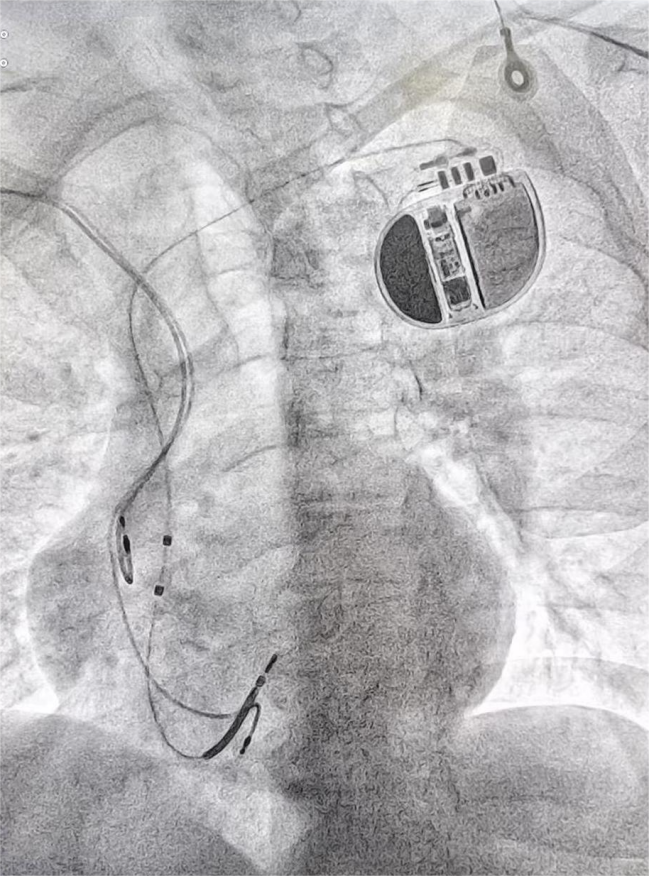

但鉴于张大爷仍有反复心律失常发作史,并且曾经出现过阿-斯综合征发作的惊险状况,为了防止悲剧再次上演,团队决定为他植入一枚 ICD(植入式心脏复律除颤器)。

ICD 是一种能够实时监测心律并及时进行电击复律的先进医疗设备,堪称是守护心脏节律的 “保镖”,可在危急时刻挽救患者生命。

在经过详细的术前准备、排除各项禁忌后,吴向军主任医师团队凭借精湛的技术,成功为张大爷完成了 ICD 植入术。手术过程非常顺利,为张大爷13年的心病,筑起了一道坚固防线。